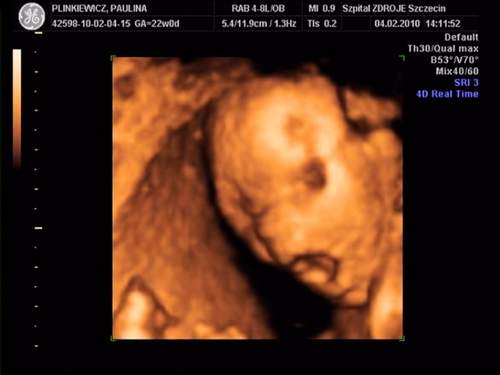

MAleńka jest super....Rozumiem że to imienniczka mojej córci - Pola!!!! Jest cudowna...Gratuluję!!!!Moja córeczka:

na drugim zdjęciu ziewa :-) a na ostatnim trzyma się za uszko:-)